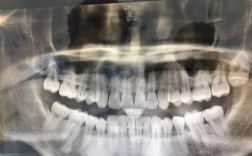

矫正牙齿期间长智齿是不少正畸患者会遇到的情况,这既可能带来口腔不适,也可能影响矫正进程,需要科学认识和妥善处理,正畸治疗多集中在青少年或青年时期,而智齿(第三磨牙)的萌出高峰年龄恰好也在18-25岁,两者时间重叠导致问题频发,矫正期间长智齿...